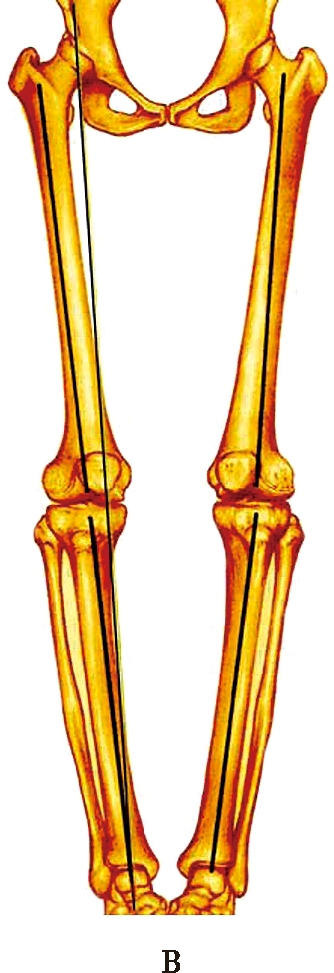

下肢负重轴

A:正常双足站立时下肢力线与下肢负重轴呈3°外翻

B:当膝关节存在内翻畸形时,膝关节中心外移,内侧关节面载荷增大

下肢负重轴即躯体垂直轴,也称躯体纵轴线。该轴线与地面垂直。双足站立时,正常下肢力线与下肢负重轴存在3°外翻。由于胫骨平台关节面存在解剖学内翻3°,因此,正常双足站立时,膝关节胫骨平台关节面与地面平行,此时内外侧关节均匀受力。当膝关节内翻时,膝关节中心外移,负重状态下,膝关节内侧负重大于外侧,从而更加重了内侧关节软骨的磨损。